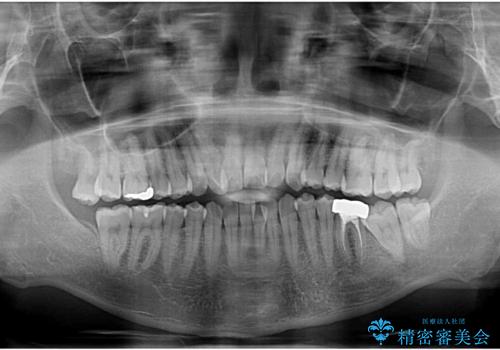

- 口元の突出感が強く、口が閉じにくいことを主訴として来院された患者さんの症例をご紹介します。

前歯部の叢生(デコボコ)も認められ、歯がきれいに並ぶためのスペースが不足している状態でした。

これらの問題を総合的に改善するため、上下左右の第一小臼歯を計4本抜歯し、スペースを確保する治療計画を立てました。

奥歯の噛み合わせがずれている「シザーズバイト」を適正に整えることで、見た目だけでなく機能性も向上し、安定した咬合が獲得できました。